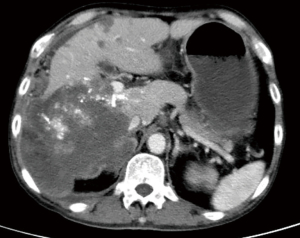

Treatment efficacy is shown in Table 2. After treatment with sorafenib and sequential regorafenib, 18 patients showed tumor progression, of which nine were treated with TACE combined with regorafenib and sintilimab, and the other nine continued to receive TACE combined with regorafenib. Five patients in the PD-1 group achieved a PR, three achieved SD, and one patient had PD after 1 month of treatment. The overall response rate (ORR) was 55.6% and the disease-control rate (DCR) was 88.9% (Table 2). One patient achieved a complete response (CR) after 6 months of therapy and another achieved a PR approaching a CR after 3 months of therapy in the PD-1 group (Figures 2,3). In the continued TACE–regorafenib group, four patients achieved PR, one achieved SD, and four patients achieved PD after 1 month of treatment. The ORR was 44.4% and the DCR was 55.6% (Table 2). No patients achieved CR after therapy, and there was a significant difference in the DCR between the two groups (P<0.05).

Our results show TACE combined with regorafenib and sintilimab confers a significant benefit when compared with continued TACE combined with regorafenib after the failure of second-line treatment with regorafenib. TACE combined with regorafenib and sintilimab had a higher DCR and was more effective than continued TACE plus regorafenib in patients with advanced HCC. Previous studies have confirmed regorafenib combined with PD-1 antibody is effective, with one showing a promising ORR of 28% in the first-line treatment of HCC (14). These results indicate TACE + regorafenib + sintilimab has an advantage over continued TACE combined with regorafenib alone. Regorafenib is a VEGFR inhibitor which inhibits JAK1/2-STAT1 and MAPK signaling, which could subsequently increase PD-L1 expression in tumors and increase intratumoral CD8+ T-cell infiltration by normalizing the tumor vasculature and improving the efficacy of the PD-1 antibody (11,15). This explains the significant difference in DCR between the two groups in our study (88.9% vs. 55.6%). However, we also found there was no significant difference in ORR between the two groups (55.6% vs. 44.4%), with four patients in the continued TACE combined with regorafenib group receiving the efficacy of PR. In other words, TACE combined with regorafenib was still effective after the failure of second-line treatment with regorafenib. This may be because the efficacy of TACE treatment differs according to patients’ physical strength and liver function. However, one patient achieved a CR and another achieved a PR approaching a CR in follow-up treatment in the TACE + regorafenib + sintilimab group, while the other group had no such efficacy. Therefore, TACE combined with regorafenib and sintilimab produced a benefit compared with continued TACE combined with regorafenib.